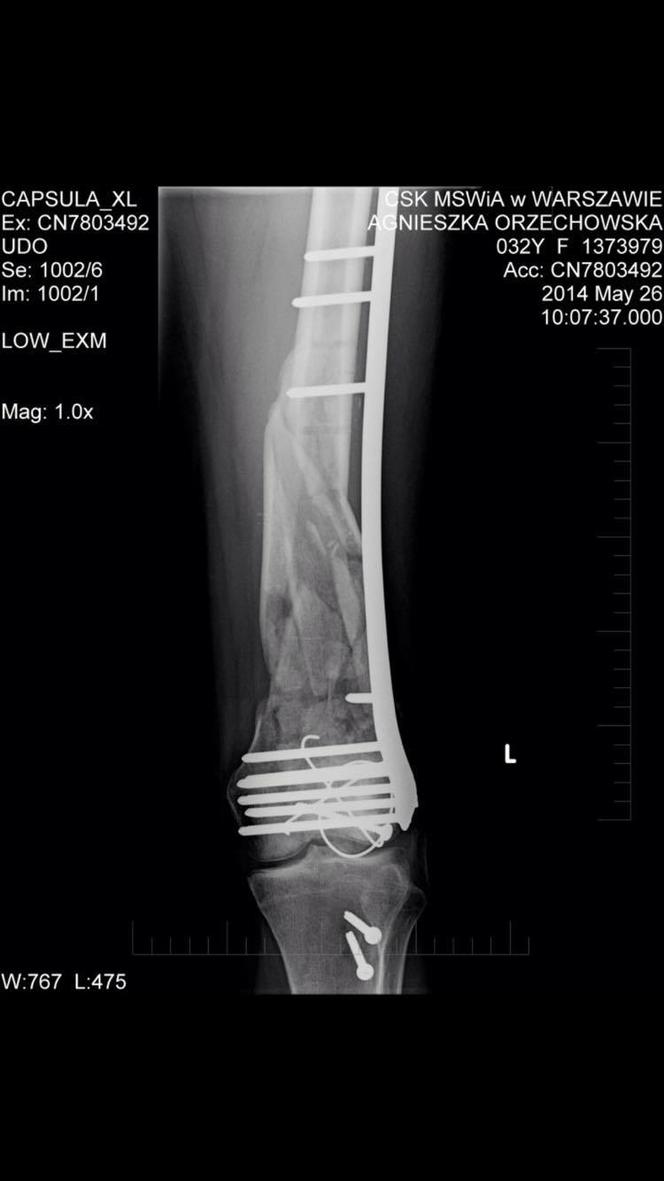

Wyrwą mi śruby z nogi